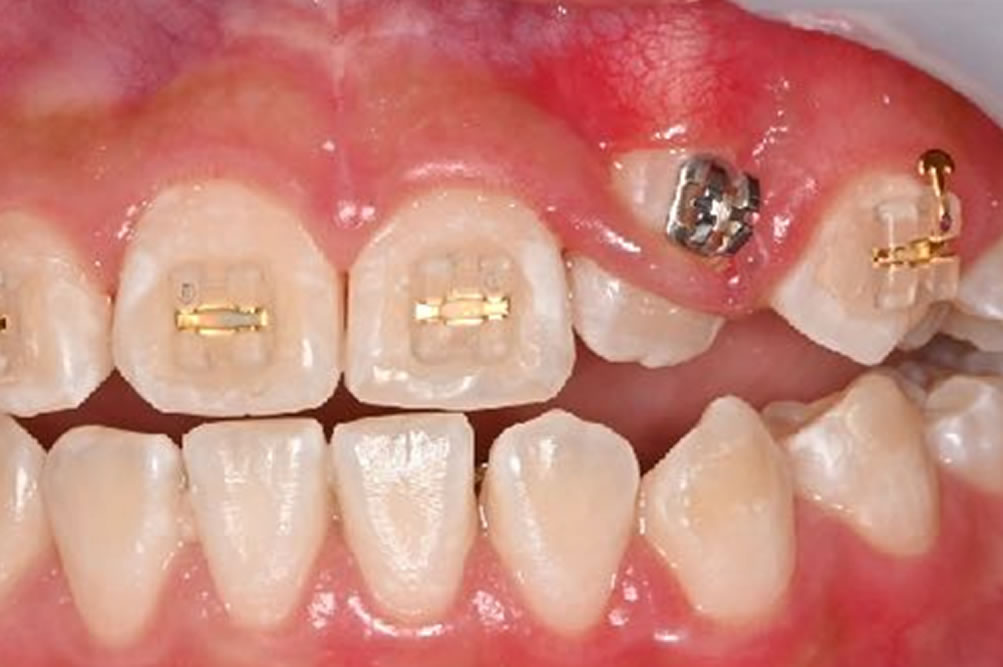

矯正後(牽引開始から6ヵ月)

牽引により萌出した歯をきれいに並べワイヤー矯正を外しました。ご家族のご協力、なにより患者さまご本人の頑張りもあり、安定したきれいな歯並び・噛み合わせを実現することができました。